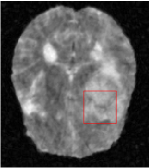

In this section, we test the generalizability of the proposed model that tests on unseen tasks. We fix the well-trained task-invariant parameter and only train for sampling ratios 15%, 25% and 35% with radio masks and sampling ratios 10%, 20%, 30% and 40% with Cartesian masks. In this experiment, we only used 100 training data for each CS ratio and apply a total of 50 epochs. The averaged evaluation values and standard deviations are listed in Table 5.4 and 5.4 for reconstructed T1 and T2 brain images respectively that proceed with radio masks, and Table 5.4 shows the qualitative performance for reconstructed T2 brain image that applied random Cartesian sampling masks. In T1 image reconstruction results, meta-learning improved 1.6921 dB in PSNR for 15% CS ratio, 1.6608 dB for 25% CS ratio, and 0.5764 dB for 35% comparing to the conventional method, which in the tendency that the level of reconstruction quality for lower CS ratios improved more than higher CS ratios. A similar trend happens in T2 reconstruction results with different sampling masks. The qualitative comparisons are illustrated in Figure 2, 4 and 5 for T1 and T2 images tested in skewed CS ratios in radio masks, and T2 images tested in Cartesian masks with regular CS ratios respectively. In the experiments that conducted with radio masks, meta-learning is superior to conventional learning especially at CS ratio 15%, one can observe that the detailed region in red boxes keeps edges and is more close to the true image, while conventional method reconstructions are hazier and lost details in some complicated tissue. The point-wise error map also indicates that Meta-learning has the ability to suppress noises.

In general supervised learning, training data need to be in the same or similar distribution, heterogeneous data exhibits different structure variations of features which hinders CNNs to extract features efficiently. In our experiments, raw measurements sampled from different ratios of compressed sensing display different levels of incompleteness, these undersampled measurements do not fall in the same distribution but they are related. Different sampling masks are shown at the bottom of Figure 1 and 2 may have complemented sampled points, in the sense that some of the points which sampling ratio mask does not sample have been captured by other masks. In our experiment, different sampling masks provide their own information from their sampled points so that four reconstruction tasks help each other to achieve an efficient performance. Therefore, it explains the reason that Meta-learning is still superior to conventional learning when the sampling ratio is large.